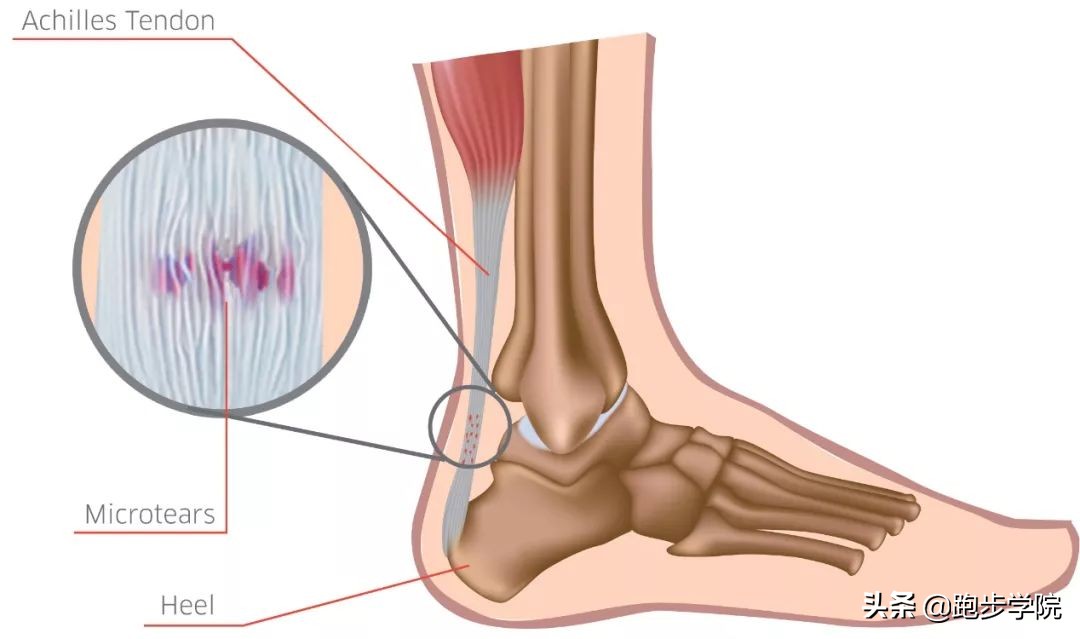

跟腱的过度使用,通常会造成超过生理极限的超负荷作用于跟腱,从而使跟腱出现细微损伤。开始时,这些细微损伤并不会造成明显不适。但出现损伤后的跟腱血液供应会逐渐变差,延长恢复时间,当再次训练时又会造成二次伤害,最终转变成严重损伤。其实这个过程和铁锈侵蚀整块铁非常像,开始并不起眼,但逐渐积累起来,最终却会引发断裂等情况。